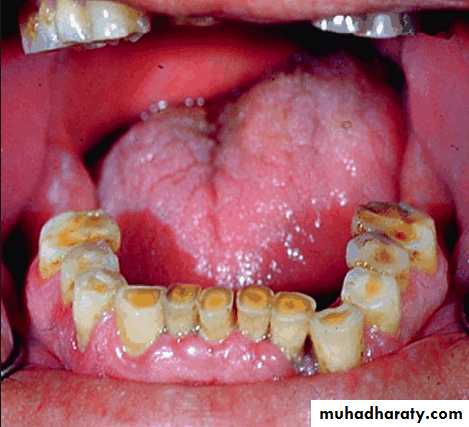

Denture stomatitis

Characterized by generalized erythema, usually including all the tissues covered by the prosthesis.Occurs under metal as well as acrylic resin denture bases, usually under maxillary prosthesis.

Frequently the mucosa is swollen and smooth – patient complaints of burning or itching.

Contributing factors:, poor fit of the prosthesis, poor oral hygiene, continuous wearing of prosthesis

Candida albicans has been shown to be present in much higher percentages of denture stomatitis patients than normal patients.

Treatment :

Remove causative factornystatin, good oral hygiene